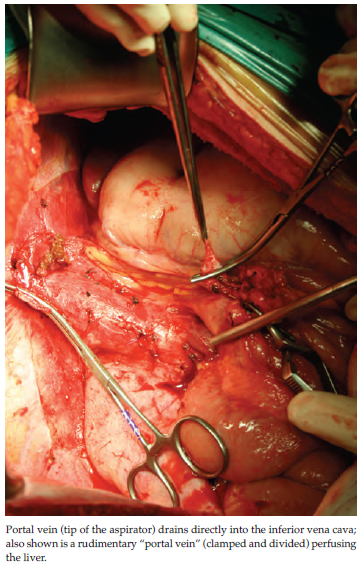

A 17-year-old girl was referred for incidentally detected multiple hepatic masses. Computed tomography and MRI showed type 1 Abernethy malformation and multiple hepatic tumors (largest was 10 cm) that appeared to be hyperplastic lesions, based on radiologic criteria. Because malignancy could not be definitely excluded, the patient received a right lobe allograft without the middle hepatic vein from her uncle. She also had a short portal vein that drained directly into the vena cava. The congenital portacaval shunt was disconnected, and the recipient’s portal vein was used to provide inflow to the graft as in patient 1. An interesting finding was that the patient also had a rudimentary “portal vein” (diameter, 3-4 mm) perfusing the liver (Figure 3).

Figure 3. Operative Field After Hepatectomy in Patient 2